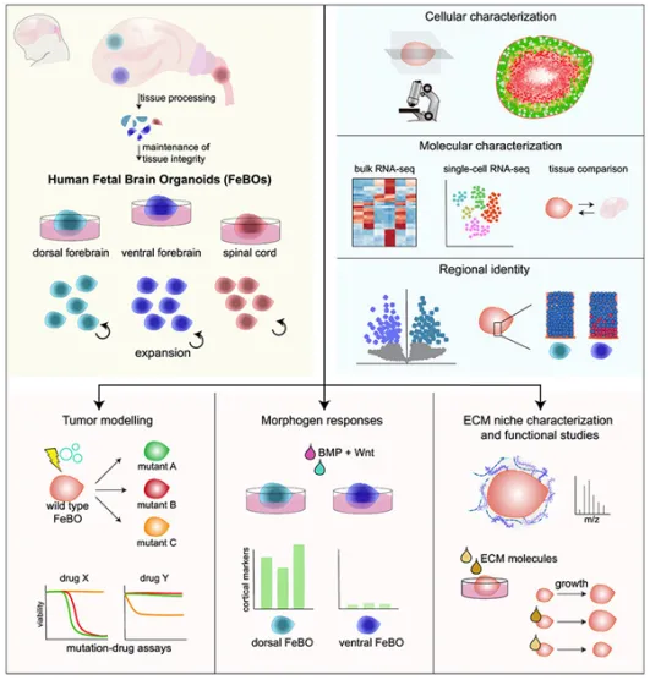

他们惊讶地发现使用小块胎儿脑组织(来自皮层、前脑和脊髓等不同大脑区域),而非原始组织分解的单细胞,竟然在体外自主生成大脑类器官(FeBOs)。

这些胎儿脑组织还产生了构成细胞外基质(ECM)的蛋白质,被认为是细胞周围的一种“支架”。科学家认为,这些蛋白质或许是大脑组织碎片能够自我组织生成3D大脑结构的重要原因。

他们还发现,这样生成的大脑类器官保留了它们来源的大脑特定区域的各种特征(可以对大脑发育中起到重要作用的信号分子做出反应)。这将有助于进一步研究脑细胞的环境,探究大脑是如何发育和分化的,有望解开这些细胞外基质如何在指导大脑发育的复杂分子网络中发挥作用的谜题。

△论文图形摘要。该研究将有助于对大脑发育的深入研究,提供脑肿瘤、大脑发育相关疾病的治疗新路径。

鉴于组织衍生的大脑类器官(FeBO)具有快速扩张的能力,科学家们还研究了它们在模拟脑肿瘤中的潜力。利用CRISPR-Cas9“基因魔剪”技术在FeBO的少数细胞中引入了众所周知的癌症基因——TP53的错误。

这个类器官模型将有助于科学家测试新的脑癌治疗药物。他们还计划使用胎儿脑类器官来研究唐氏综合征等神经发育障碍疾病。

为了进一步研究脑肿瘤与基因突变的关系,科学家使用CRISPR-Cas9技术关闭了与脑胶质母细胞瘤(Glioblastoma,胶质母细胞瘤是星形细胞肿瘤中恶性程度最高的胶质瘤)相关的三个基因:TP53、PTEN和NF1。经由基因突变的类器官可以观察它们对现有肿瘤药物的反应。

通过CRISPR-Cas9基因编辑技术,科学家在实验中实现了用于脑肿瘤研究的基因突变大脑类器官模型,FeBO构成了一个互补的中枢神经系统类器官平台。并且在肿瘤药物研究中,具有将某些药物与特定基因突变联系起来的潜力,有望为脑肿瘤患者精准用药和个体化治疗提供新方案。